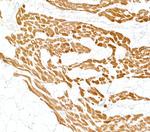

Cardiac Troponin I Monoclonal Antibody (16A11)

高级验证

WB IHC ELISA IP AP